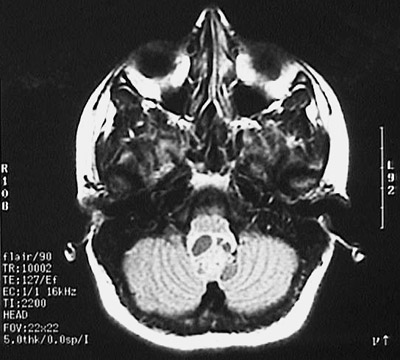

| This computed tomographic (CT) imaging scan demonstrates a discrete mass filling the fourth ventricle. This is an ependymoma, the most common neoplasm at this site, and a common place for an ependymoma. There is some cystic change in this ependymoma. |